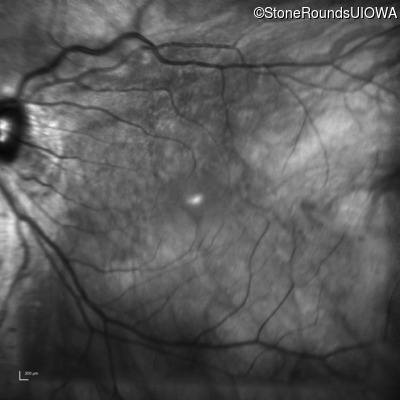

Infrared Fundus Photograph - Right - 20/40 +2

Exemplar